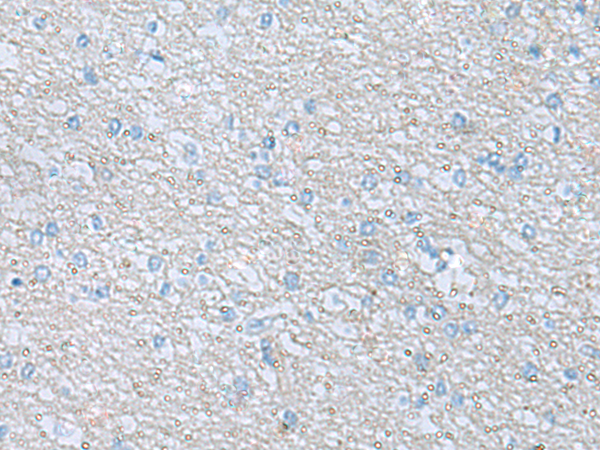

分类: 科研抗体货号: P12434别名: XKR2; XRG2; XPLAC应用: WB,IHC反应种属: Human